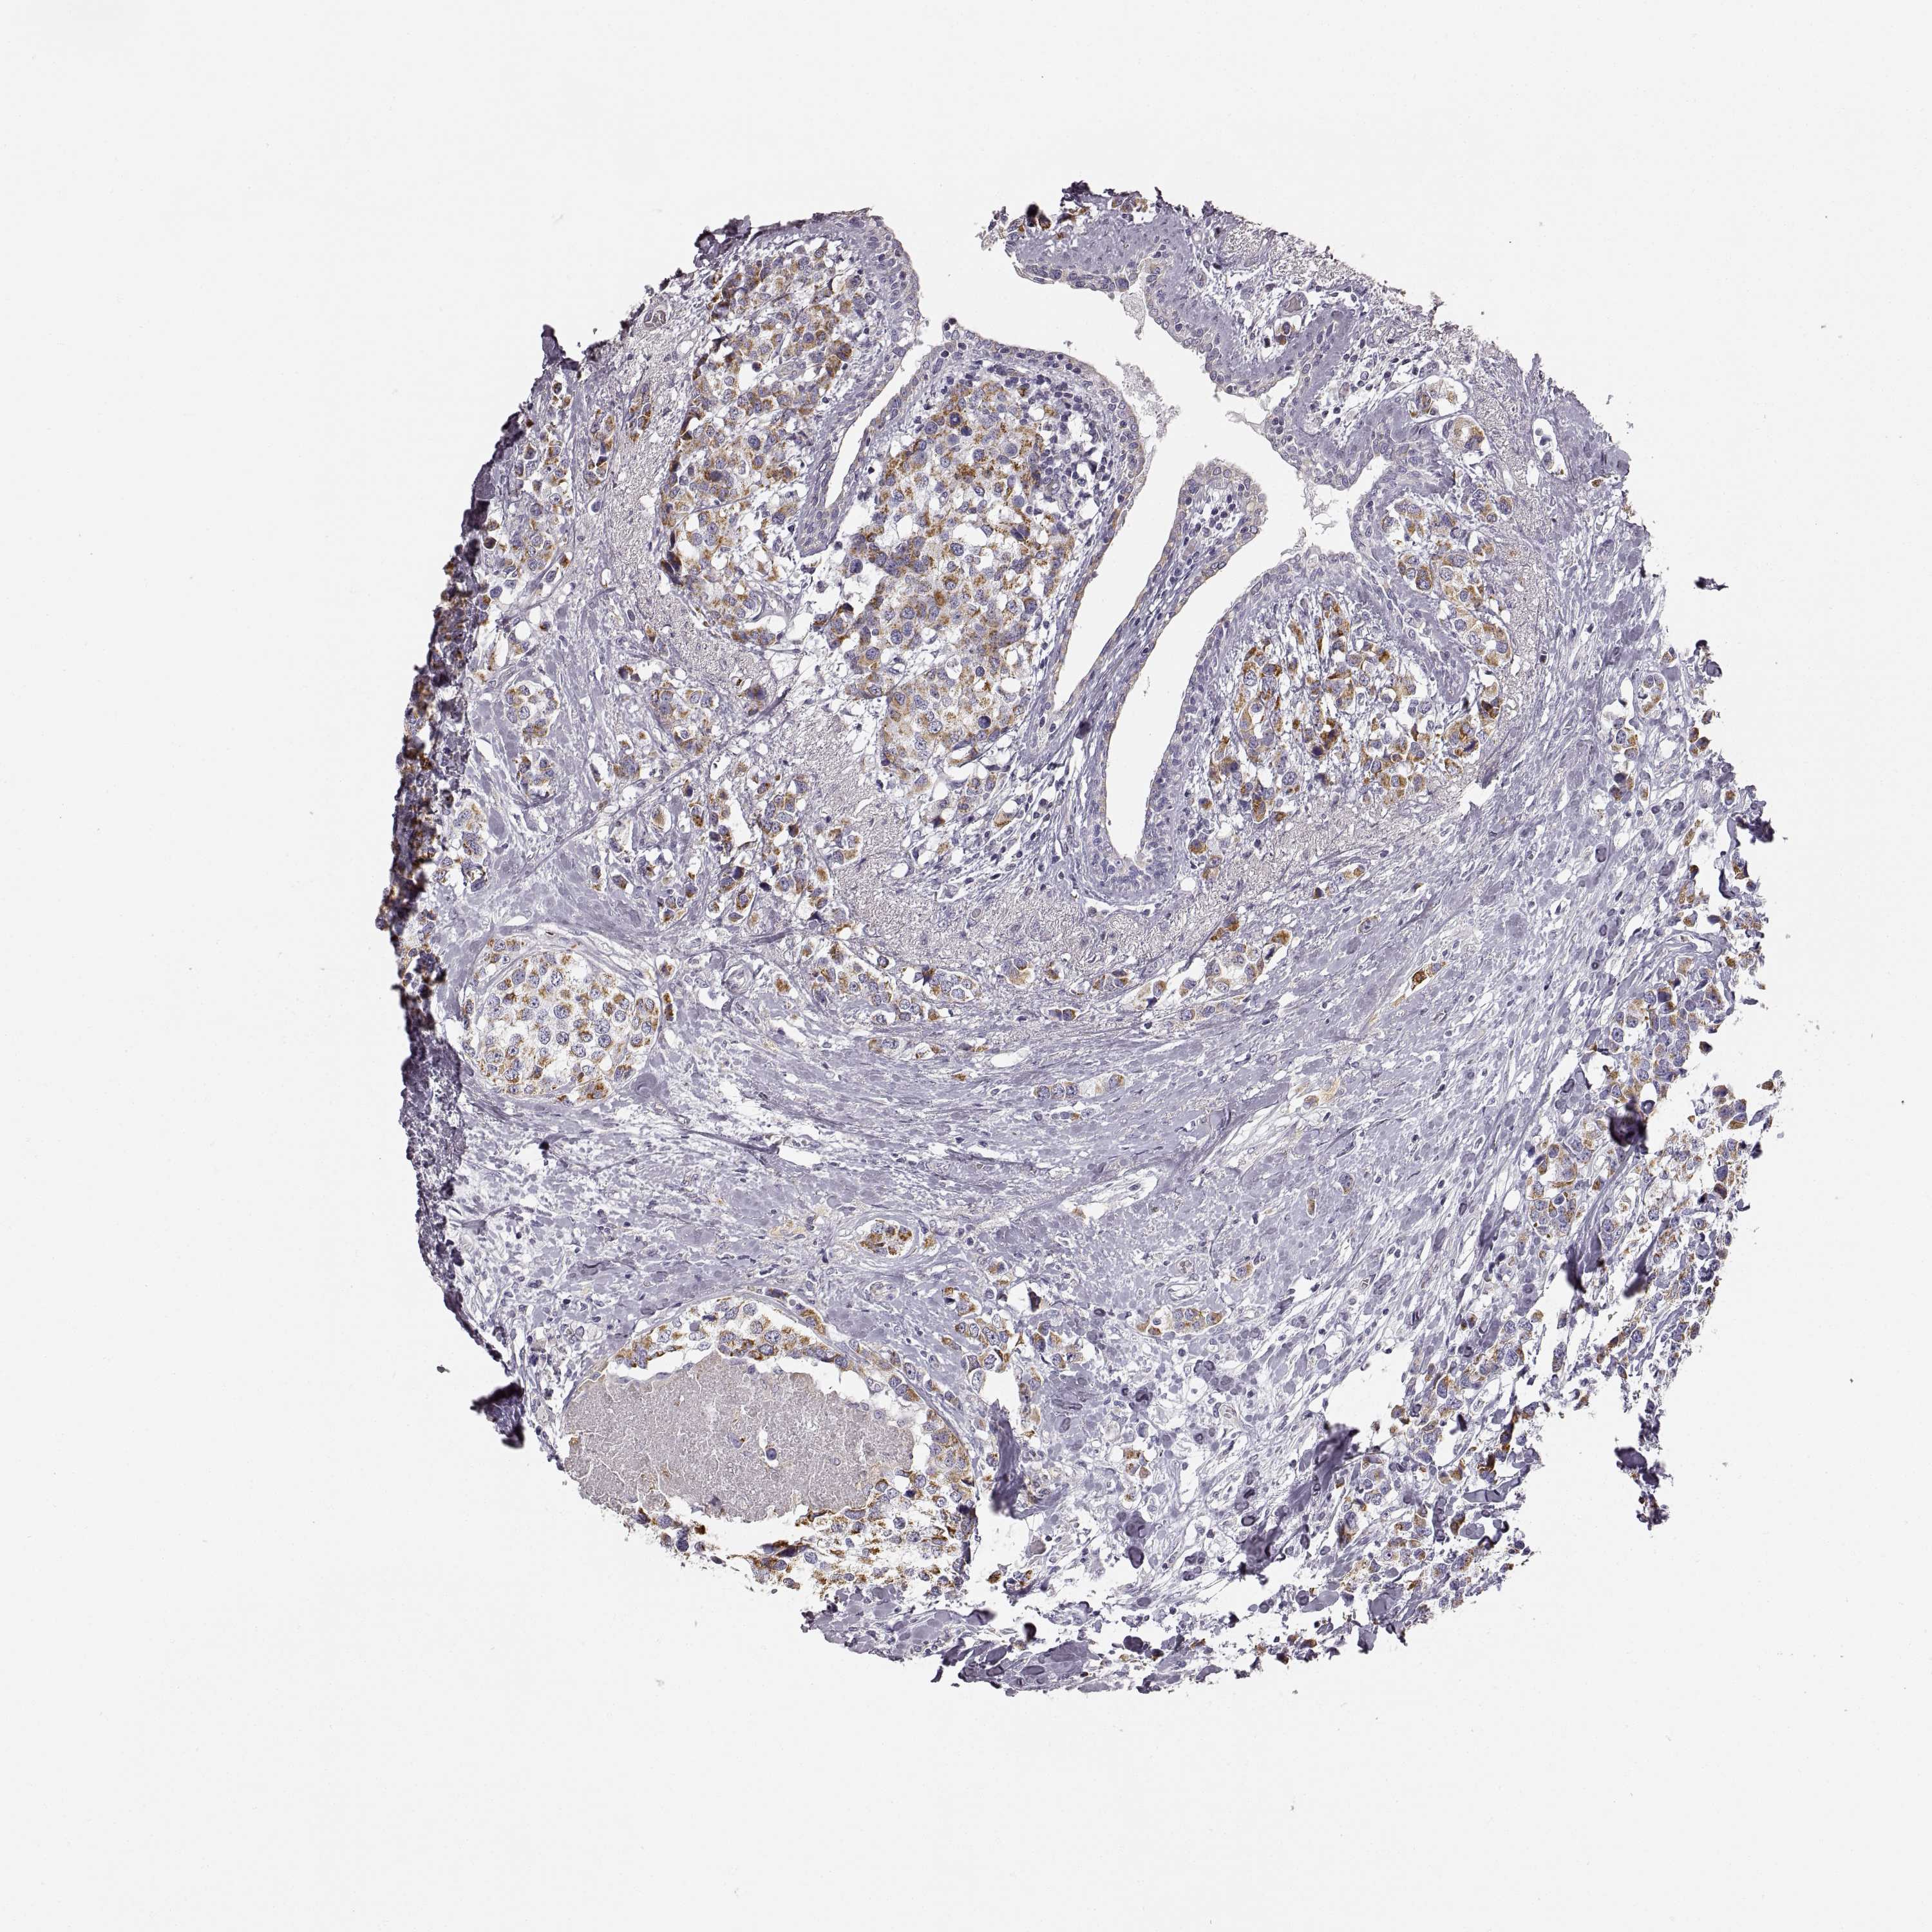

CANCER BREAST CANCER Show tissue menu

BRCA TCGA BRCA VALIDATION PROTEIN EXPRESSION